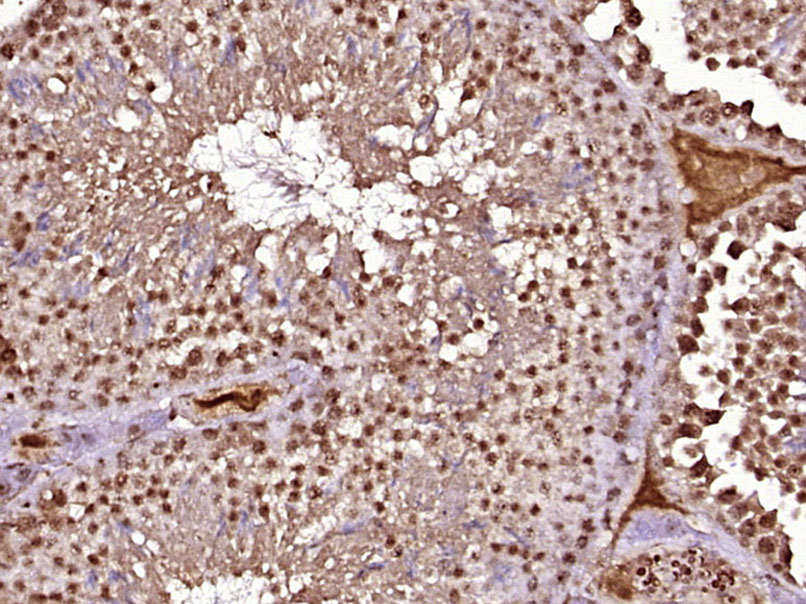

| 英文名称 | SCCPDH Rabbit pAb |

| 中文名称 | 酵母氨酸脱氢酶抗体 |

| 产品应用 | IHC-P=1:100-500, IHC-F=1:100-500, IF=1:100-500 Not yet tested in other applications. |

| 交叉反应 | Mouse (Human, Rat, Dog, Pig, Cow, Horse, Rabbit, Sheep) |

| 背景资料 | SCCPDH is a 429 amino acid protein that belongs to the saccharopine dehydrogenase family. The SCCPDH gene is conserved in chimpanzee, dog, cow, mouse, rat, chicken, fruit fly, mosquito and C.elegans, and maps to human chromosome 1q44. Chromosome 1 is the largest human chromosome spanning about 260 million base pairs and making up 8% of the human genome. There are about 3,000 genes on chromosome 1, and considering the great number of genes there are also a large number of diseases associated with chromosome 1. Stickler syndrome, Parkinsons, Gaucher disease and Usher syndrome are also associated with chromosome 1. A breakpoint has been identified in 1q which disrupts the DISC1 gene and is linked to schizophrenia. Aberrations in chromosome 1 are found in a variety of cancers including head and neck cancer, malignant melanoma and multiple myeloma. |

| {IHC-P} | {1:100-500} |